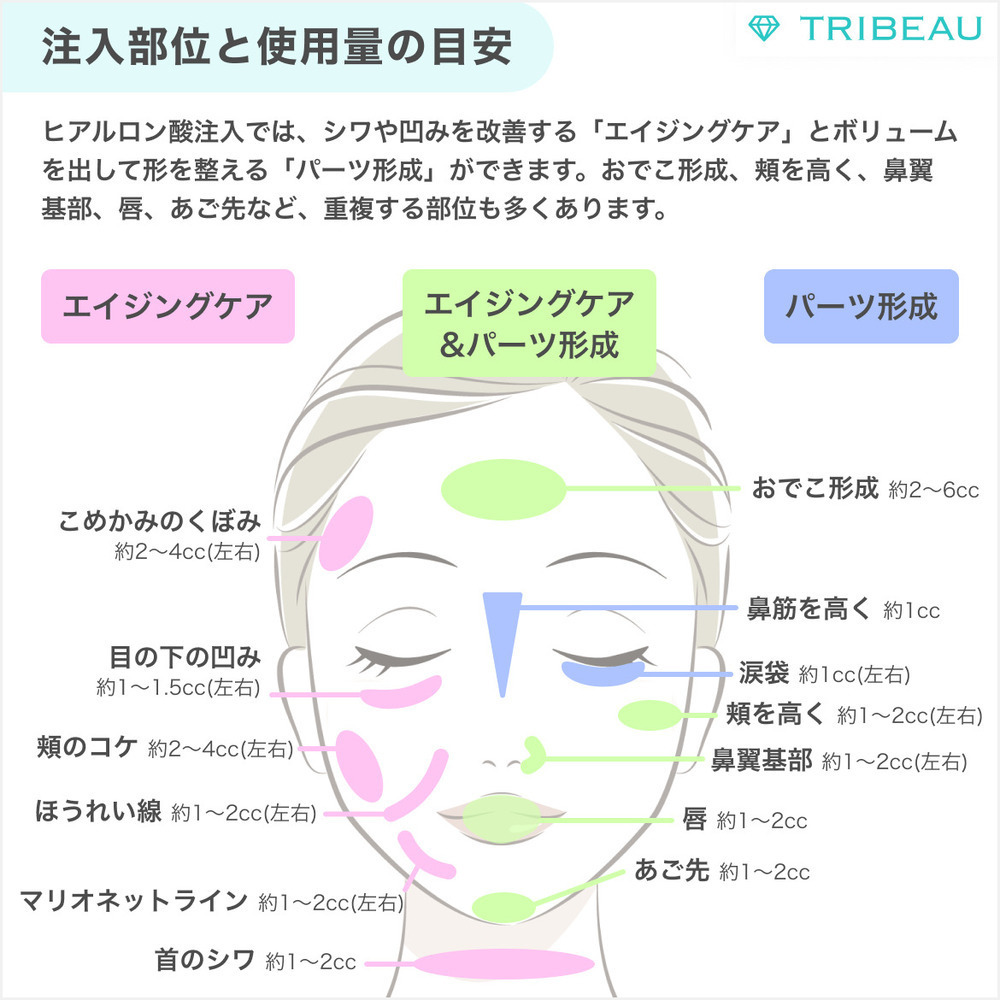

額にヒアルロン酸を注入することで、立体感のある丸いおでこにする施術です。

リスク・副作用

内出血腫れ赤みむくみ痛み感染塞栓